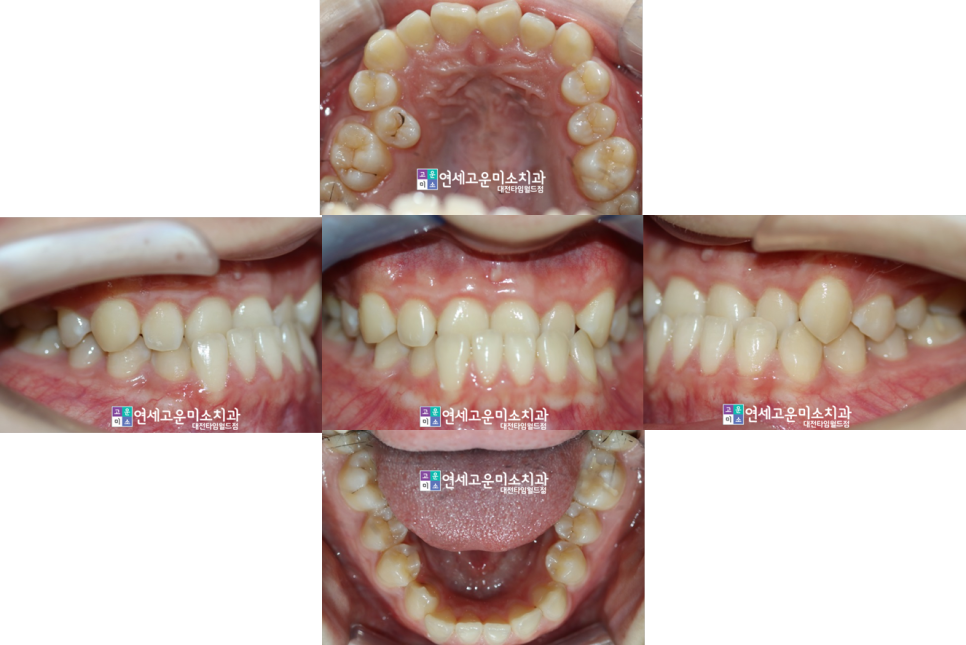

발치치료 후의 모습입니다

입술 각도가 많이 줄어든 것을

확인할 수 있습니다.

엑스레이에서 보면 호두턱 양상도

개선이 되었습니다.

입안 사진을 보면 중심선도 개선되었고

교합도 개선이 된 것을 확인할 수 있습니다.